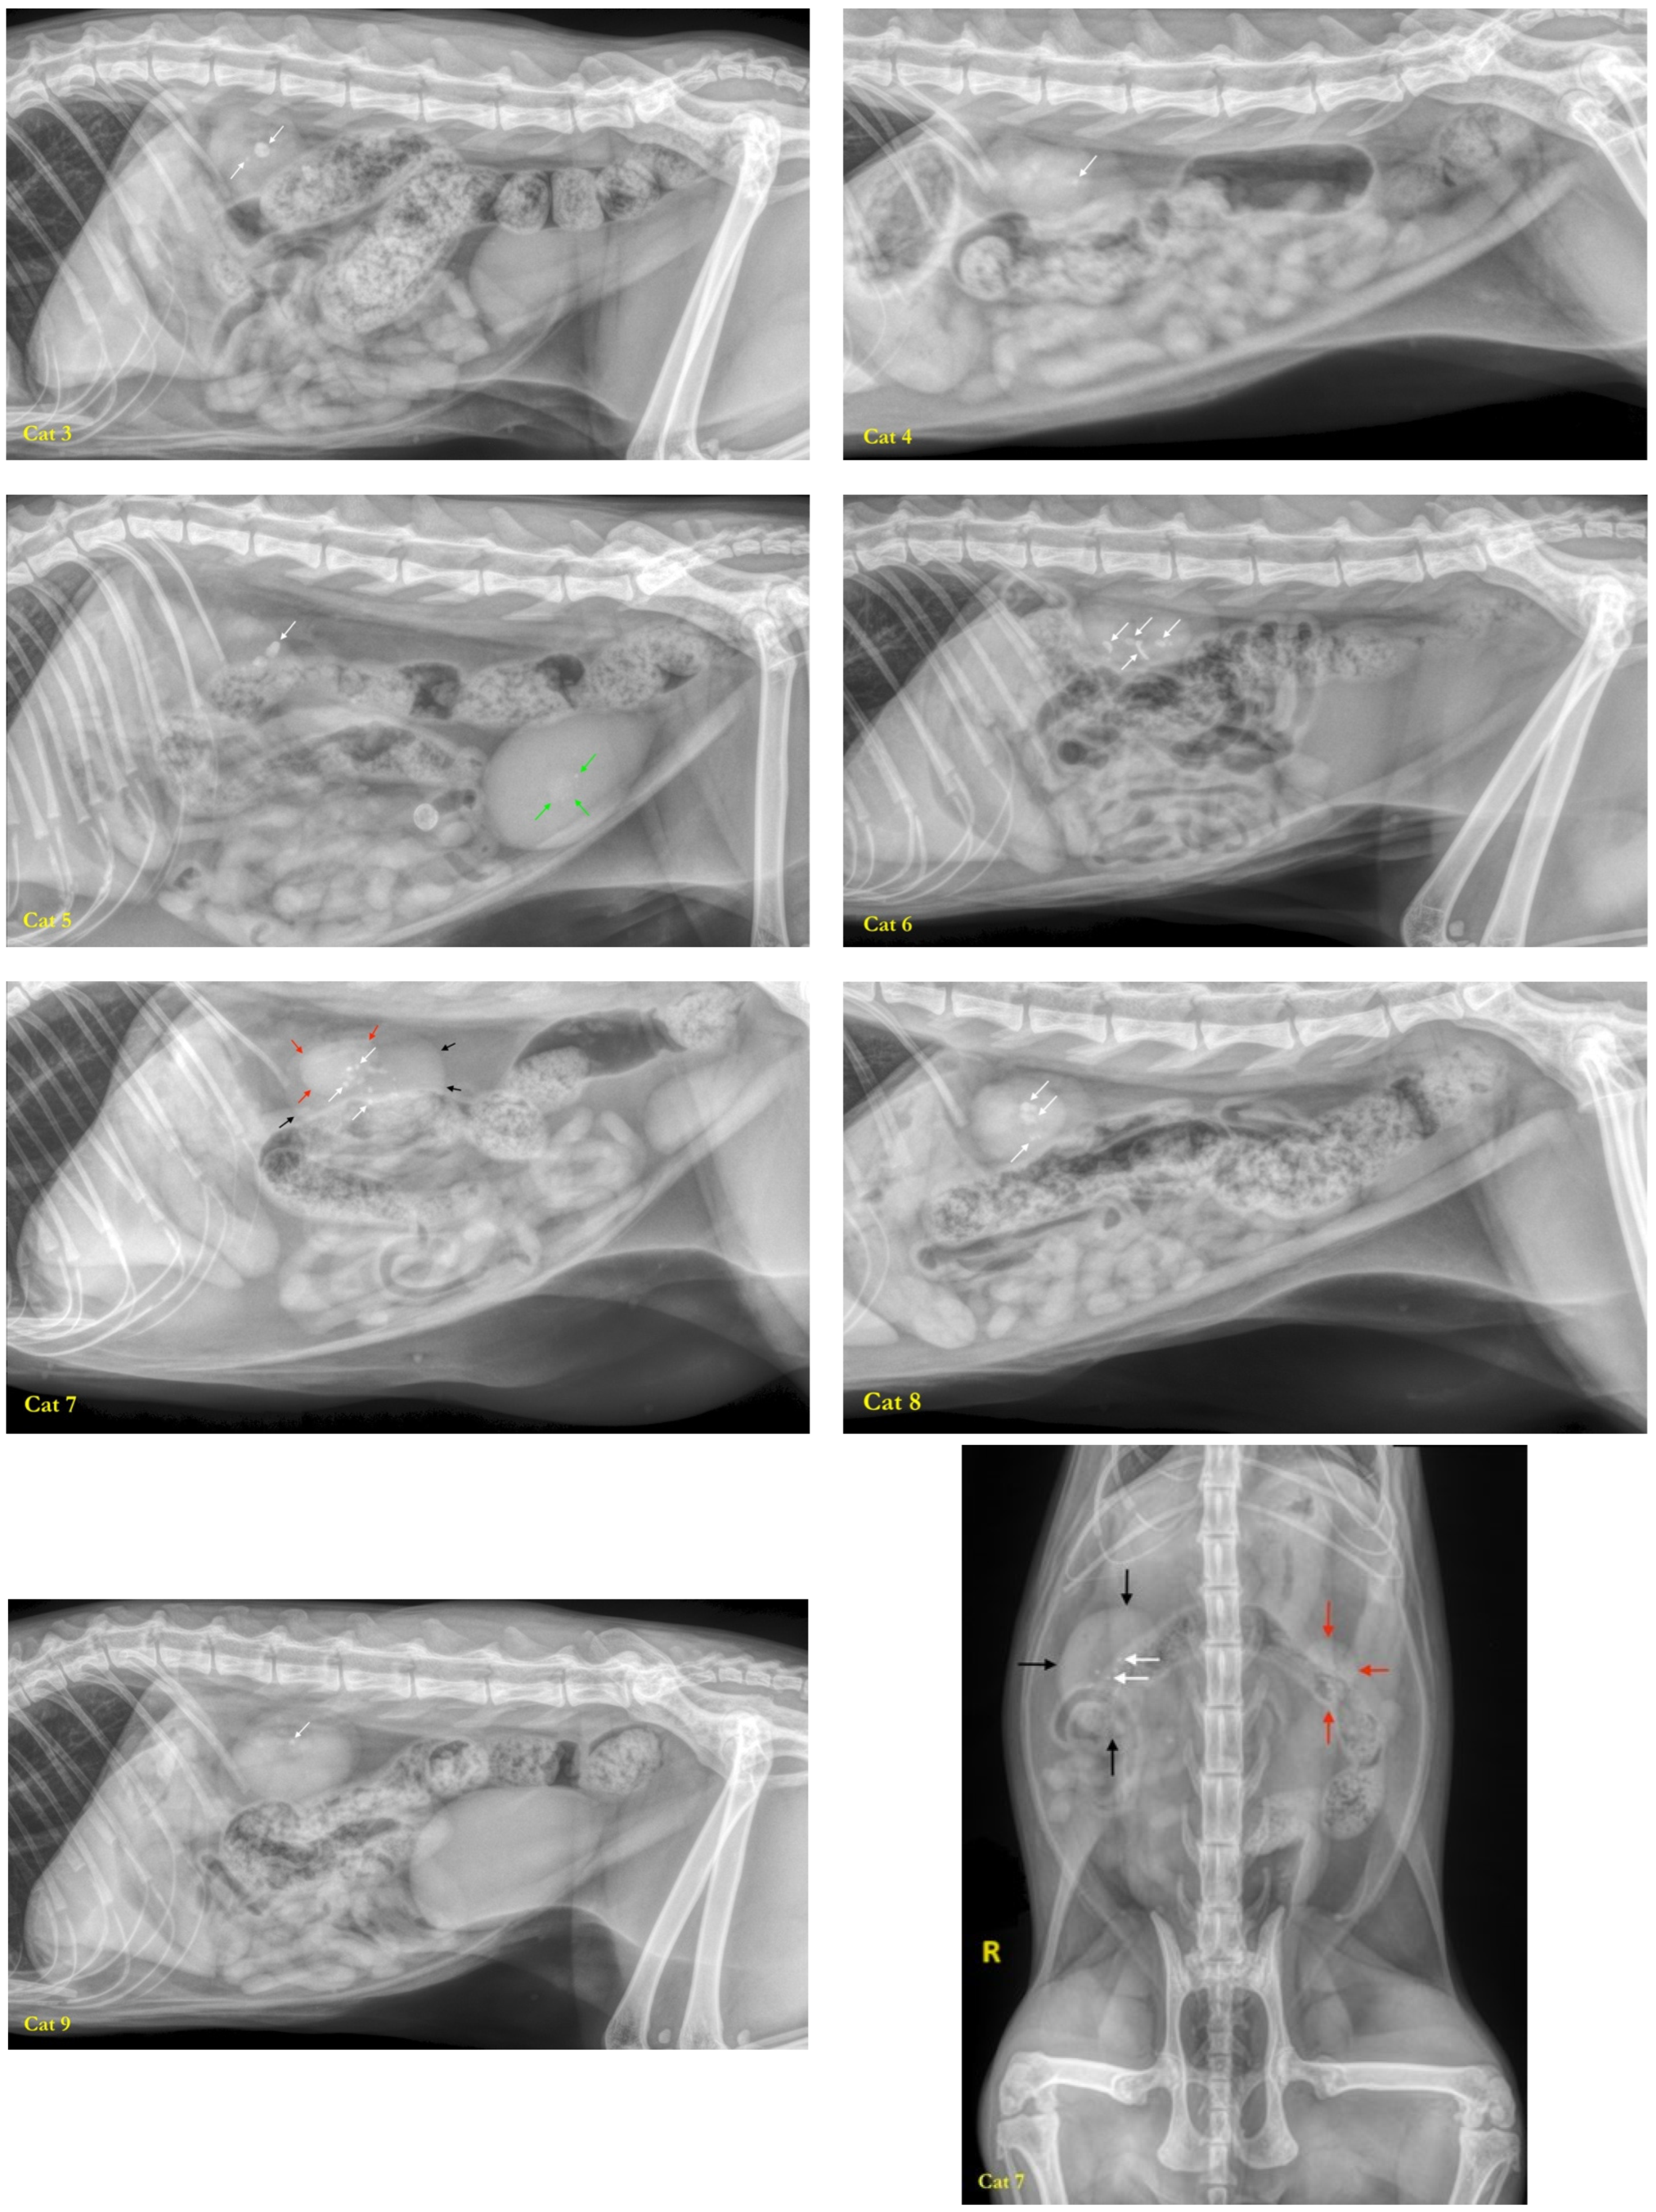

2.1. Studied Population

2.1.1. Recruitment of Cats

2.1.3. Health Status

2.1.4. Inclusion Criteria

2.1.5. Exclusion Criteria

3.1. Studied Population